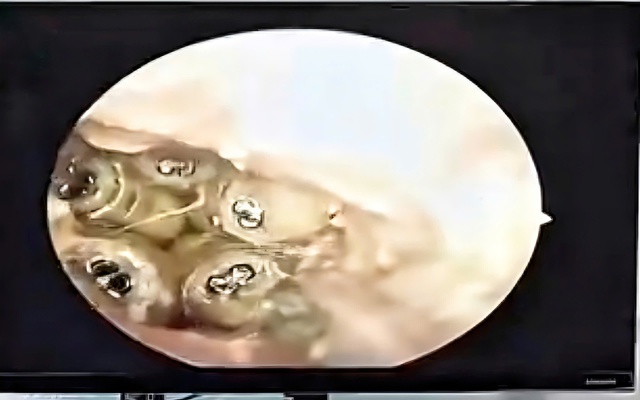

5 con giòi sống trong tai bệnh nhân

ẢNH: CẮT TỪ CLIP

Sau khi hút sạch dịch trong ống tai, các bác sĩ đã gắp ra 5 con giòi còn sống cùng xác một con côn trùng nằm sát màng nhĩ. Theo nhận định của bác sĩ, do bệnh nhân không thể tự chăm sóc bản thân, trong quá trình sinh hoạt có thể côn trùng đã chui vào tai, làm tổ và đẻ trứng, sau đó trứng nở thành giòi.